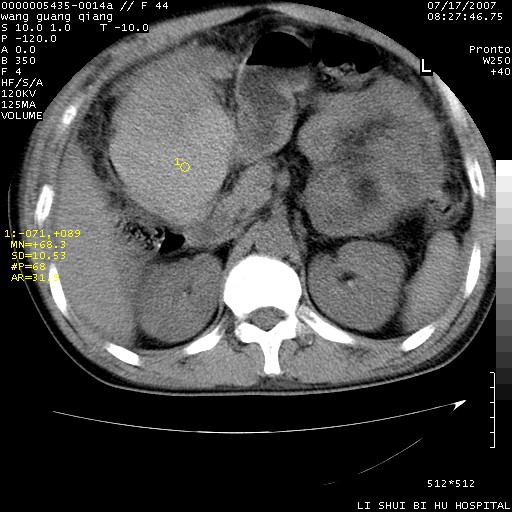

以下是引用dyqct在2007-7-18 10:46:00的发言:[br]胆囊明显增大,壁增厚,明显强化;后下方见大片高密度区,ct值68hu,无强化,周围见多数条纹状高密度影,边界不清。双膈下间隙、肝肾隐窝见带状及片状低密度区。[br]右侧胸壁后缘亦见新月形水样密度区。[br]考虑:1、急性胆囊炎伴周围出血;[br] 2、少量腹水、右侧少量胸腔积液。[br][br][本贴已被 dyqct 于 2007-7-18 10:48:47 修改过]